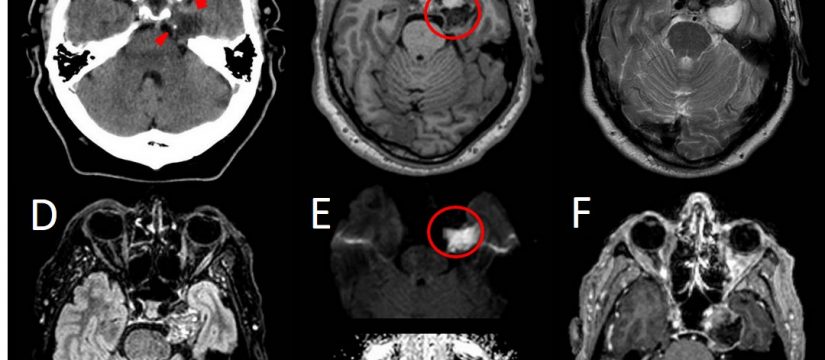

Historia Clínica

Varón de 40 años con esclerosis múltiple remitente-recurrente ya conocida, que consulta por disartria de varios días de evolución.